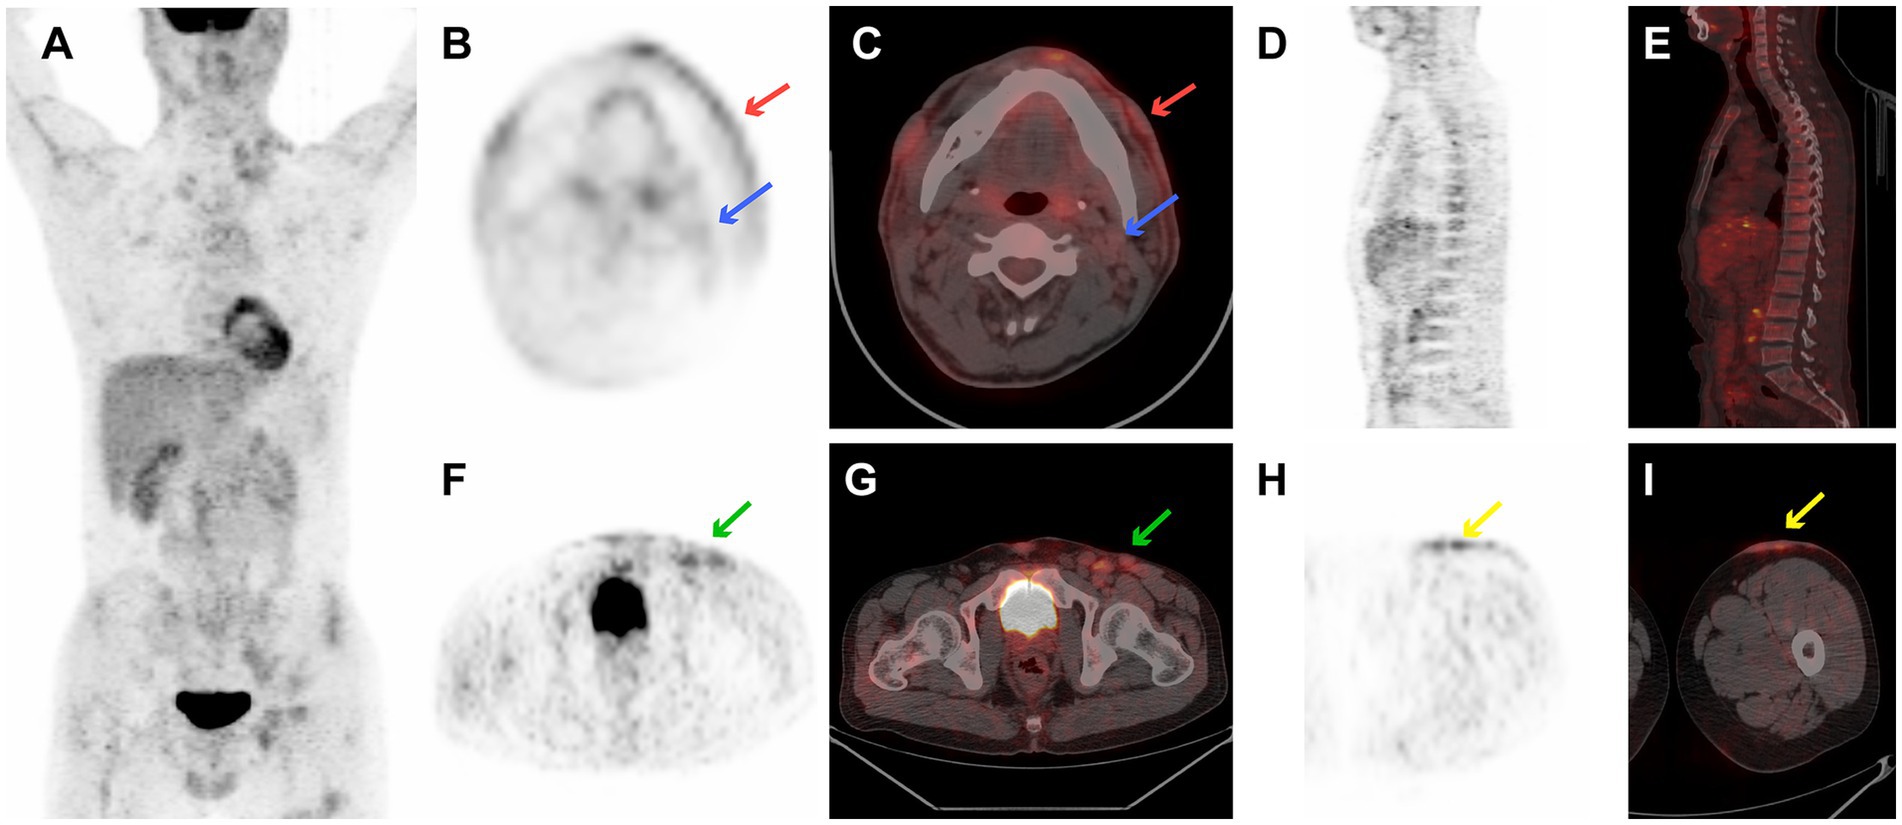

A 36-year-old man presented with a 5-month history of a nodular violaceous rash on the skin and multiple lymphadenopathies. He had no specific medical history. Physical examination revealed multiple nodules over his head, neck, chest, and back, and in the left femoral region, together with multiple enlarged lymph nodes in the bilateral neck, bilateral armpits, left groin, and bilateral supraclavicular areas. The complete blood count revealed pancytopenia (hemoglobin = 58 g/L, white blood cell = 3.2 × 10 9/L, and platelet = 4 × 10 9/L).18F-FDG PET/CT image is illustrated in Figure 1. Figure 1 shows the 18F-FDG PET/CT images of case 4, with disseminated cutaneous, lymph nodes, and extranodal localization disease (Figure 1A). 18F-FDG PET/CT revealed multiple mild-to-moderate FDG-avid cutaneous lesions on his head, neck, chest, and back, and in the left femoral region with an SUVmax of 2.6 (the SUV of the liver was measured at 2.7). Supra- and infra-diaphragmatic abnormally enlarged lymph nodes were seen in cervical, supraclavicular, axillary, mediastinal, retroperitoneal, and left bilateral inguinal areas with an SUVmax of 3.7 (Figures 1B,C,F–I). Mild FDG-avid in the trunk bone was detected with an SUVmax of 1.5 (Figures 1D,E). This patient underwent a skin biopsy, cervical lymph node biopsy, and bone marrow examination, all of which indicated BPDCN. He died from gastrointestinal bleeding due to abnormal coagulation function 15 days after diagnosis.

Figure 1

18F-FDG PET/CT images of case 4 revealed multiple mild-to-moderate FDG-avid cutaneous lesions on the head, neck, chest, back, and left femoral region with an SUVmax of 2.6. There are supra- and infra-diaphragmatic abnormally enlarged lymph nodes with an SUVmax of 3.7. Mild FDG-avid of trunk bone was detected with a SUVmax 1.5. (A) PET maximum intensity projection (MIP), (B) transverse PET image of cutaneous lesion of cheek (red arrows) and cervical lymph nodes (blue arrow), (C) transverse fused PET/CT image of cervical cutaneous lesion of cheek (red arrows) and cervical lymph nodes (blue arrow), (D) sagittal PET image of bone, (E) sagittal fused PET/CT image of bone, (F) transverse PET image of left inguinal lymph nodes (green arrow), (G) transverse fused PET/CT image of left inguinal lymph nodes (green arrow), (H) transverse PET image of cutaneous lesion in left femoral region (yellow arrows), and (I) transverse fused PET/CT image of cutaneous lesion in left femoral region (yellow arrows).